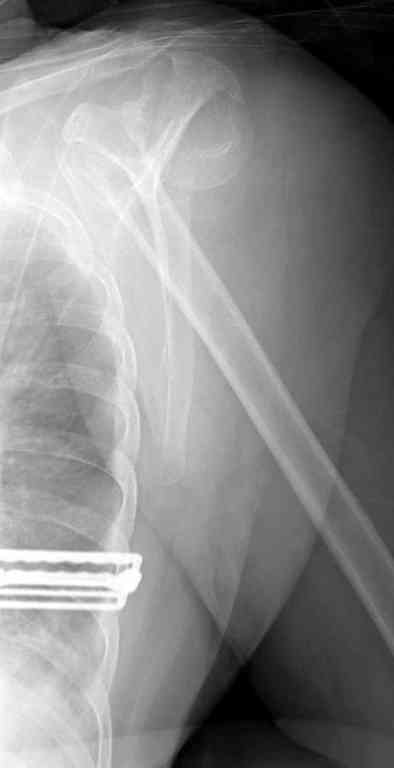

Сделали напряженными спицами по методике А.Ф.Лазарева со товарищи Репозиция сделана спицевым дистрактором, проксимальная спица была проведена в полскости деформации перпендикулярно оси наклонившейся головки. Получилось все довольно легко. Спицы малость покороче можно было сделать, ну да удалять потом легче будет.

Картинка в приложении.

Очень даже неплохо получилось. Молодцы! Лучше чем на 3D "репозиции".